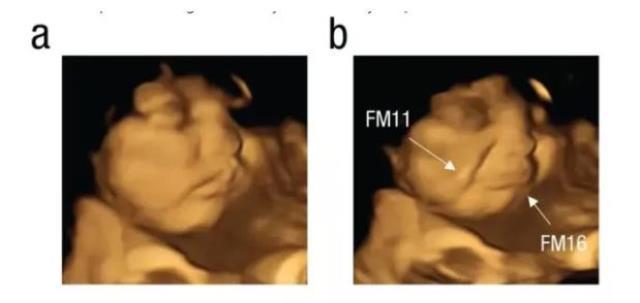

Yapılan bir araştırma kapsamında hamile kadına lahana tozu yedirildi, ardından da karnındaki bebek görüntülendi. Bebeğin yüzünü ekşittiği anlar ise saniye saniye ultrason kamerasına yansıdı.

Çalışmaya katılan anne adaylarının raporlama öncesinde herhangi bir gıda tüketmemesi talep edildi. Çalışma kapsamında bir grup anne toz havuç tüketirken diğer grup ise lahana tozu yedi. Lahana tozuna maruz kalan bebeğin, yüzünü ekşittiği görüldü. Fetüslerin reaksiyonunu doğumdan önce gösteren ilk çalışma olarak nitelendirilirken makalede imzası olan Dr. Benoist Schaal da sonuçların bu kadar net olmasını şaşırtıcı olarak değerlendirdi.